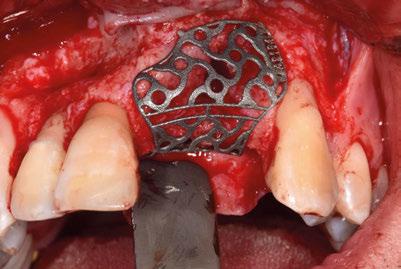

–Implante inmediato en incisivo lateral superior con técnica de «Socket Shield» y acceso vestibular para legrado de la lesión periapical, por el Dr. Ignacio Tormo Jiménez y cols. [106]